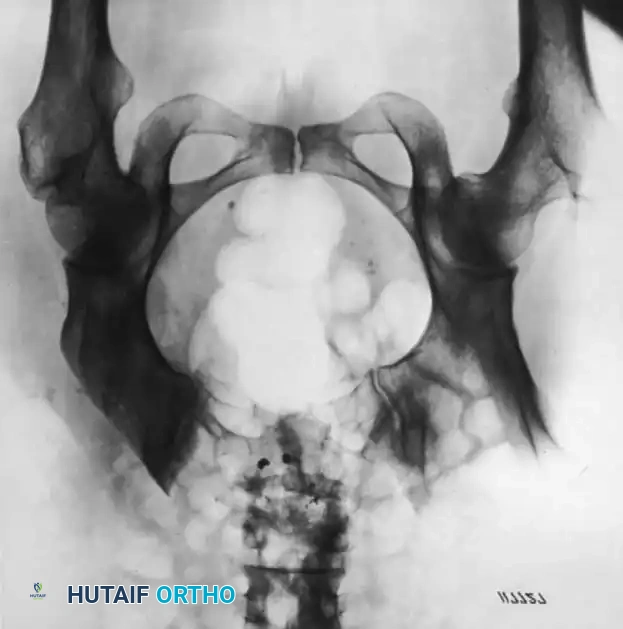

عظام الحوض وجناح الحرقفة

يتكون الحوض من عدة عظام مندمجة، ويعتبر جناح الحرقفة الجزء العلوي العريض منها. ترتبط بهذا العظم مجموعة كبيرة من العضلات الأساسية، مثل عضلات البطن وعضلات الألوية. في حالات العدوى العميقة والمزمنة التي تسبب تصريفاً صديدياً مستمراً، يمكن استئصال جزء كبير من جناح الحرقفة للسيطرة على العدوى، مع إعادة ربط العضلات لضمان الحفاظ على الوظيفة الحركية.

جراحة استئصال جناح الحرقفة

قد يكون استئصال جزء كبير من جناح الحرقفة ضرورياً في حالات التهاب العظم والنقي المزمن في الحرقفة المصحوب بتصريف مستمر لفترات طويلة. تتضمن الجراحة إجراء شق فوق العرف الحرقفي، وفصل العضلات الألوية وعضلات البطن والعضلات الأخرى المرتبطة بالعظم بشكل تحت سمحاقي. يتم استئصال الحرقفة ككتلة واحدة إلى الحد المطلوب، وتوضع أنابيب تصريف لضمان خروج السوائل بشكل فعال.